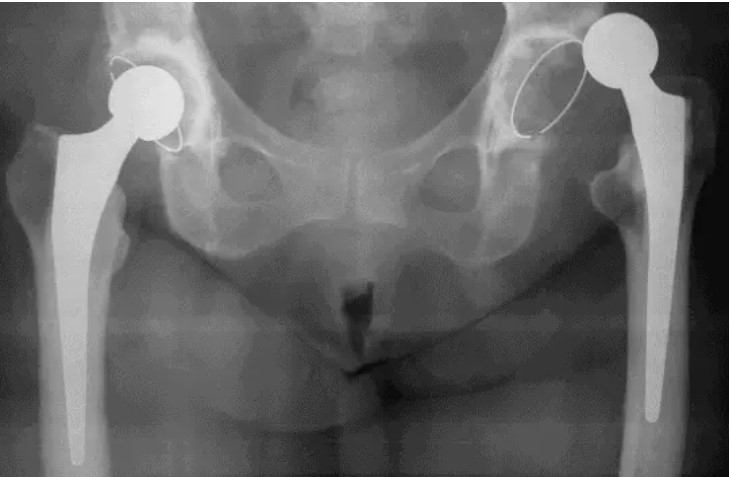

Чаще всего для диагностики используется рентгенография тазобедренного сустава с выполнением в нескольких проекциях. Этот метод позволяет определить положение головки эндопротеза относительно чашки. На рентгеновском снимке видна целостность компонентов и наличие или отсутствие переломов.